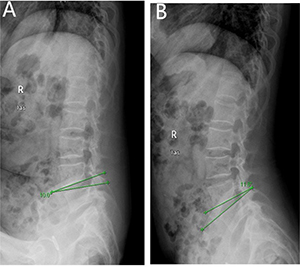

Figure 2: Angular motion of a 48 years old man,diagnosed with discogenic low back pain (LBP) for 2 years. (A) delineates flexion angle measured by X-ray (L4-5). (B) indicates the extension angle measured by X-ray (L4-5).

X-ray is also widely used to help the diagnosis of discogenic LBP as the angle motion, defined as difference of the flexion and extension angle, can describe degree of the hypermobility. Hypermobility is also thought to play an important role in the IVDs degeneration as IVDs bears major load in humans [23]. Discogenic LBP is mainly due to IVDs degeneration and such process is defined by changes in architecture and biochemical composition that invariably alter the internal mechanical environment of the disc. The anular fibers become torn and disorganized, the nucleus becomes less hydrated and it is difficult to distinguish the border between the anulus and nucleus [10]. Those changes contribute to altering the constraints placed on adjacent vertebrae, leading to spinal hypermobility. Such type of mechanical exposure initiates damage from the outside and then works inward via anular delamination and disruption, cellular metaplasia, and vertebral rim hypertrophy as anular fibers is the peripheral disc tissue that acts to restrict intervertebral movement [24]. Ariga et al. [25] have also linked hypermobility to the development of cellular apoptosis and matrix damage within the cartilage end plate by using a mouse mode. The results show that patients in the study group owns much more Angle motion when compared with the patients in the control group (19.09 ± 3.44 vs 10.33 ± 3.02; P = 0.00), and the it is also the factor showing high diagnostic significance of the lumbar discogenic pain based on the multivariate analysis (p = 0.020) and ROC curve (AUC = 0.978).

Angle motion of the lumbar spine intervertebral was measured to indicate the degree of spine instability and include angle motion and lumbar mobility [32].Two lines across the upper and lower vertebral body margin of lesion level insect and form the angle at flexion and extension position by X-ray (Phillips,Eindhoven, Netherlands), difference of the flexion and extension angle was defined as the angle motion of lumbar spine [33]. Lumbar mobility was measured by calculating the distance between upper and lower vertebral body of the lesion level at the lateral position by X-ray. The cobb angle of interest is simply the angle between the two line drew from the upper endplate of the upper body and along the lower endplate of the lower body [34]. Height of the lesion disc was measured by supine MR (Siemens,Germany). The T1 and T2 intensity images were constructed with the TE/TR of 10/500 ms and 100/2800 ms. The slice thickness was 4 mm. We performed the measurement on the T2 intensity images at the sagittal planes. The measurement of the vertical intervertebral disc lengths was performed on the mid-saggital section of the vertebral body (anterior, middle and posterior). Measurement of spinal canal dimensions of the lesion level (saggital diameter and transverse diameter) was carried out by supine MR to reflect degree of the lumbar spinal stenosis [35]. HIZ was defined as a small, round zone with limited high-intensity signals in the posterior annulus of lumbar intervertebral discs on sagittal slices of T2-weighted MR, it also represents a deep radial fissuring the annulus fibrosis of the lesion level, just as revealed by lumbar CT discography [36–39]. Modic changes are usually displayed by MR to describe the signal intensity changes of vertebral end-plate of the lesion disc [40]. Modic type 1 changes (MC1) refers to low T1 and high T2 signal, MC2 refers to high T1 and T2 signal, and MC3 refers to low T1 and T2 signal [41]. Grading of disc degeneration was assessed from T2-weighted sagittal images based on the Pfirrmann method [31]. Two independent spine surgeons performed the measurement by using Centrieity Enterprise Web V3.0 (General Electric,US).